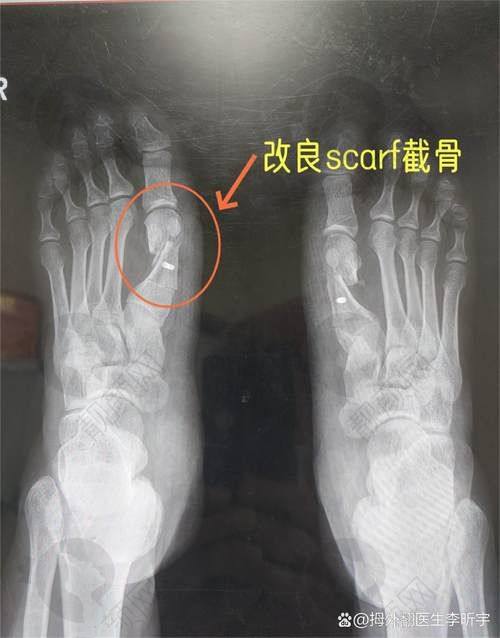

在大脚骨拇外翻矫正方面,苏敬达医生技术实力特别强。他采用小创口技术进行手术,实现了术后即刻行走的目标,大大减少了手术中的疼痛和不适。

他采用的小创口术式,手术切口小、创伤小、修复快,能更好地保护周围组织,减少手术风险和并发症。手术过程中采用局部麻醉,让患者在手术时感受不到足部疼痛,意识还清醒,没有恐惧心理,比传统手术的腰部麻醉风险更低,患者体验更好。

他在手术中非常重视细节,使用专有的精细足雕仪器进行手术,确保手术操作的稳定性和精细性。还会根据患者的实际情况进行个性化设计,让手术结果更加自然和美观。而且由于小创口手术创伤小、修复快,患者在手术后当天就能下地走路,疼痛感轻微,能更快地回归正常生活和工作。